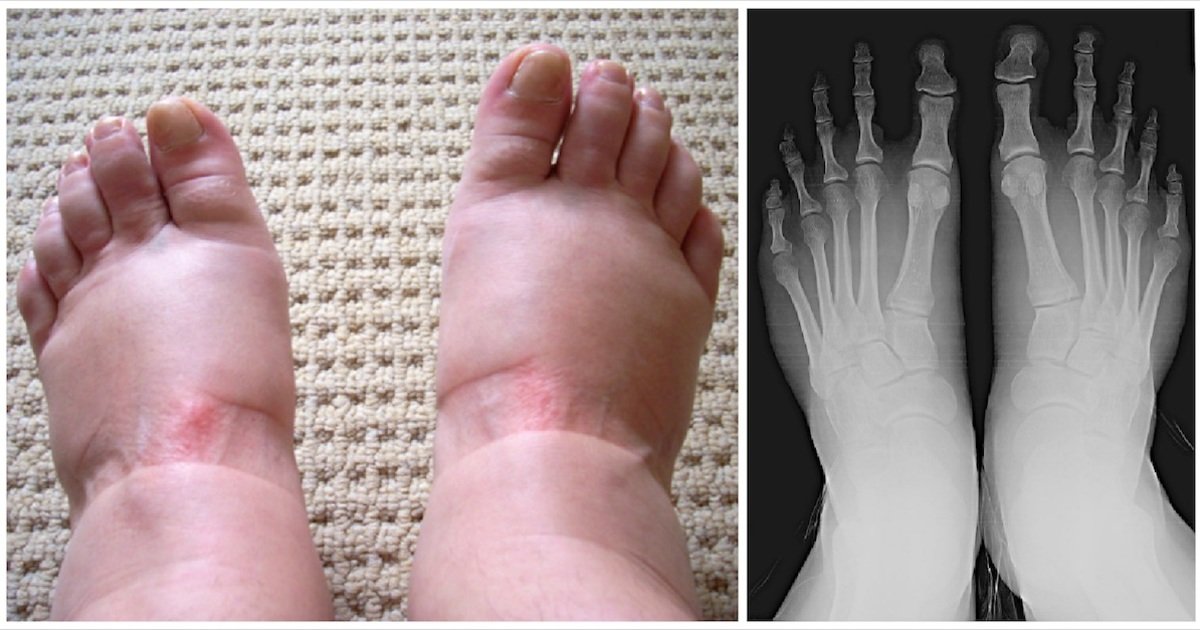

Decoding Edema: A Guide to the Medical Causes of Swollen Hands and Feet

Medically referred to as edema, swelling in the hands and feet is a common symptom with a wide range of potential causes, from benign to